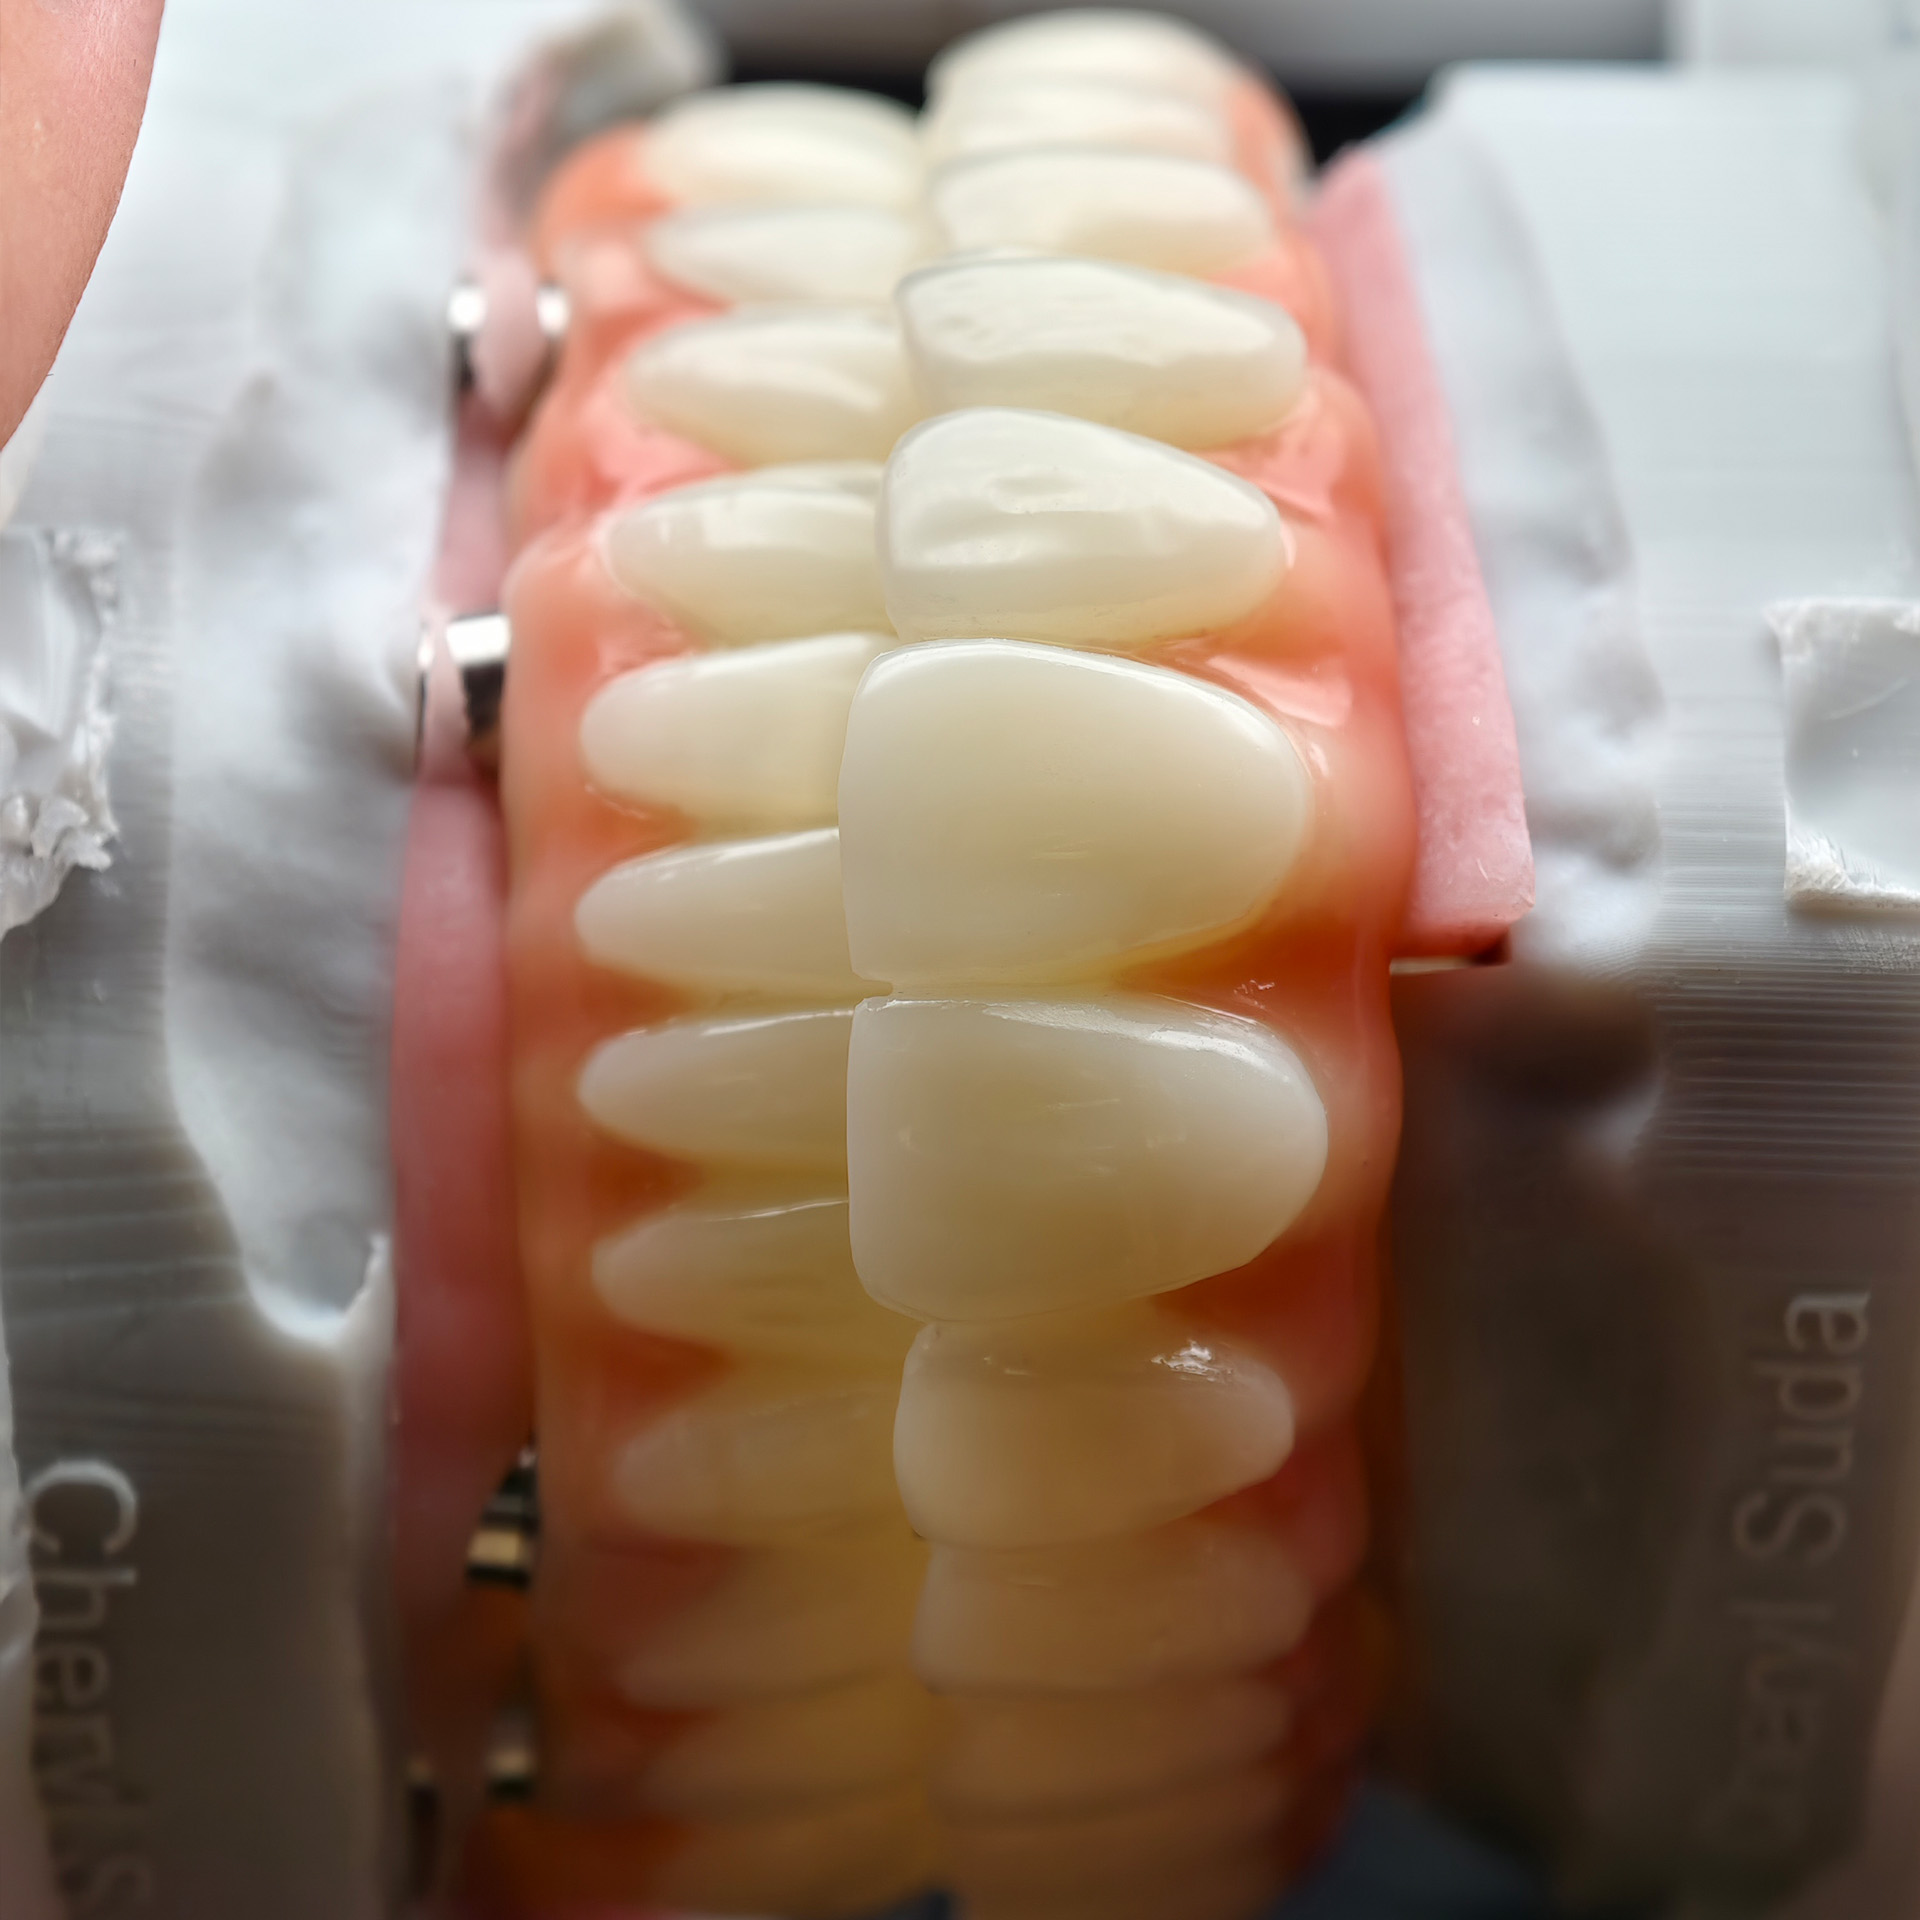

Products Description

An pmma bridge

A pmma bridge is a type of dental restoration made from polymethyl methacrylate (pmma), a durable and aesthetic plastic. It's commonly used for temporary or long-term provisional restorations, especially in full-arch implant cases, and is known for its strength, flexibility, and ability to be screw-retained for easy removal and adjustment.

Key characteristics of pmma bridges:

Material:

pmma is a type of acrylic plastic that is biocompatible and relatively strong.

Purpose:

Temporary restorations: Often used during the healing phase after dental implant placement, or while permanent restorations are being fabricated.

Long-term provisional restorations: Can be used for extended periods, particularly in cases like full-arch implant restorations where a permanent

solution may take time.

Trial bridges: Allow patients to "try out" a new smile before committing to a permanent restoration.

Screw-retained:

pmma bridges can be designed to be screw-retained, allowing for easy removal and adjustment by the dentist.

CAD/CAM Technology:

pmma bridges can be fabricated using CAD/CAM technology, ensuring a precise fit and good aesthetics.

Aesthetics:

pmma can be made in various shades to match a patient's natural teeth.

Durability:

While durable, PMMA is not as wear-resistant as some other materials like zirconia and may be more prone to breakage or staining over time.

PMMA bridges are a versatile and effective solution for various dental needs, offering a combination of strength, aesthetics, and ease of use, particularly in implant dentistry.